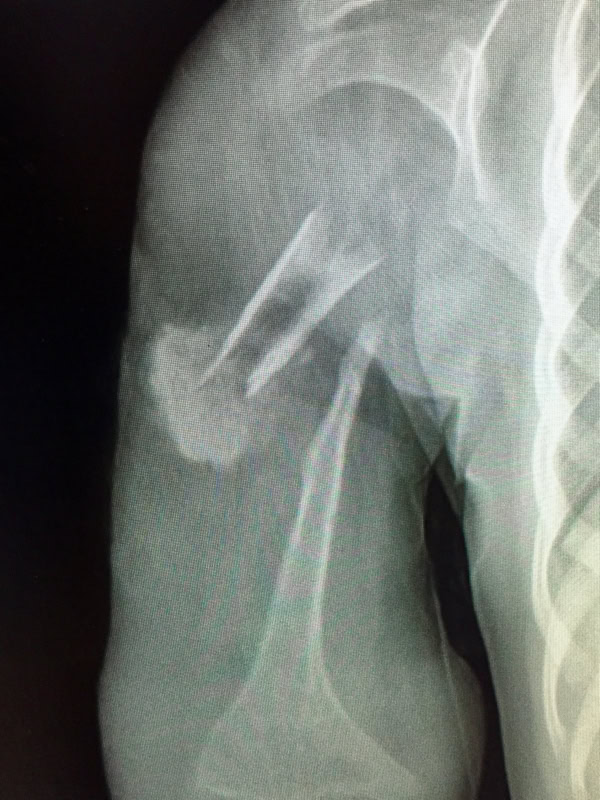

In the print version of the book there are many black and white images. The full colour versions are found in the gallery below. Depending on your connection performance the enlarged images may take a little time to load.